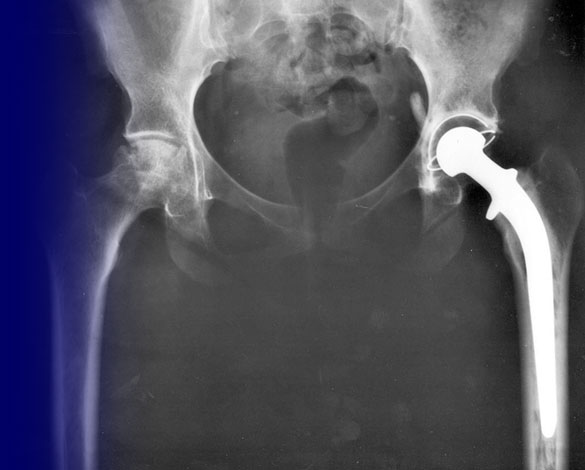

Prosthetic Implant

Photo: National Institutes of Health/Wikimedia • Placed in the Public Domain